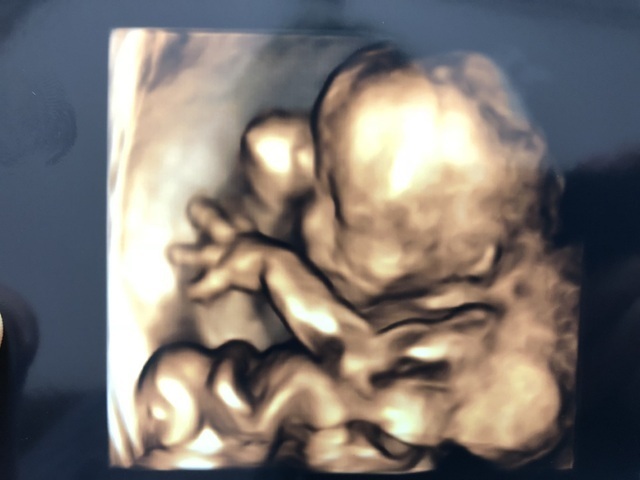

20週5日(20w5d・男の子)|たくさき3710 さん(28歳)

エコー写真撮影時のエピソード:

初めての4Dエコーでお顔を見れるのをとっても楽しみにしていました!ですが胎盤に顔を押しつけるようにしたままあまり動かず、ほぼずっと横顔しか見せてくれませんでした。

このエコーはその中でも貴重な、少しだけこっちを向いてくれた瞬間の物で、偶然左手の親指をしゃぶっていました! 次は34wで4Dエコーの予定なので、お顔をたくさん見せてくれるといいな!